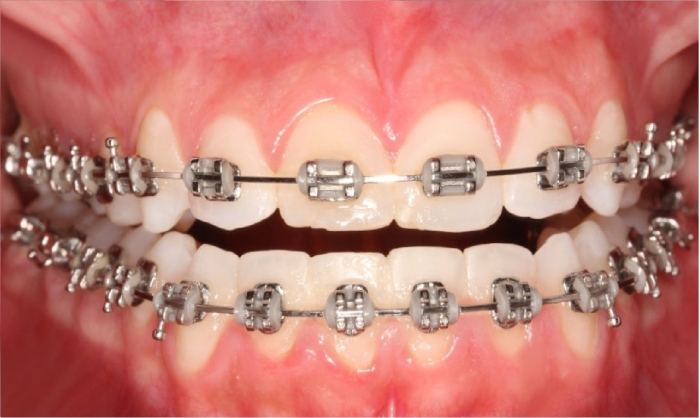

Mordida inicial